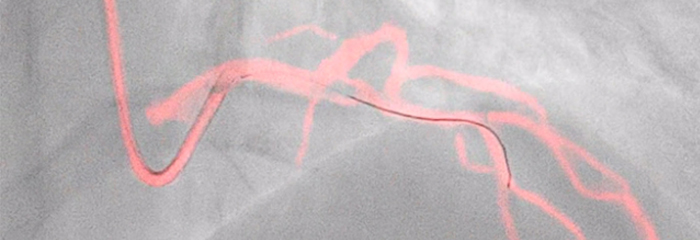

Interventional cardiology procedure for coronary artery disease

Dynamic Coronary Roadmap

Dynamic Coronary Roadmap, a Philips-exclusive technology, creates a motion-compensated, real-time view of coronary arteries. Recent evidence demonstrates that DCR can reduce contrast agent by 28.8% during a PCI procedure. With DCR a highlighted coronary angiogram is superimposed on a live 2D fluoroscopic image, creating a colored roadmap that adjusts automatically, providing continuous visual feedback on positioning of wires and catheters.